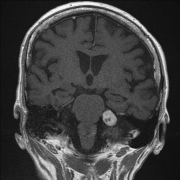

聽神經(jīng)瘤預(yù)后如何?聽神經(jīng)瘤復(fù)發(fā)了怎么辦?聽神經(jīng)瘤在女性中比男性更常見,通常影響老年人(40至60歲)。聽神經(jīng)瘤是一種生長緩慢的良性腫瘤,不會擴散到腫瘤的原發(fā)部位以外。如果...